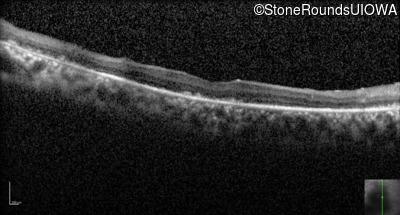

Optical Coherence Tomography - Right - 20/1000 sc

Exemplar / OCT Stack

OCT Stack

Optical Coherence Tomography - Left - 20/500 sc

Infrared Fundus Photograph - Right - 20/1000 sc